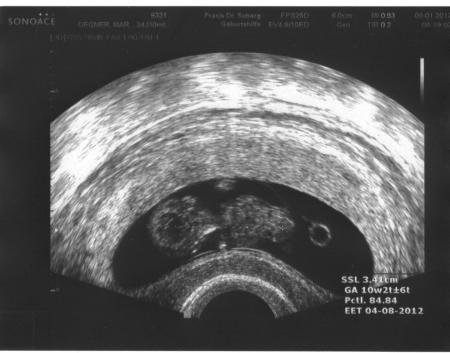

Hallo Mädels, ich bin zurück von meinem Fa- Termin und freue mich seeeeehhhhhrrrrr! Sieht alles ganz gut aus, nur das sie mich um eine Woche zurück setzt (erstmal) ET neu wäre der 13.08. Wir lassen es aber so und schauen, wie es sich in 2 Wochen entwickelt hat. Herzchen schlägt kräftig und es hat mit den Armen gewackelt. Es ist 2,6 cm groß! Ach ich bin soooooo glücklich. Jetzt hole mich mir noch einen Termin für das Ersttrimester- Screening! Habt ihr eure Termine schon? Freudige Grüße Katja Das ist mein Schatz ----->

Bild zu Zurück vom Fa! - Forum für August - Mamis